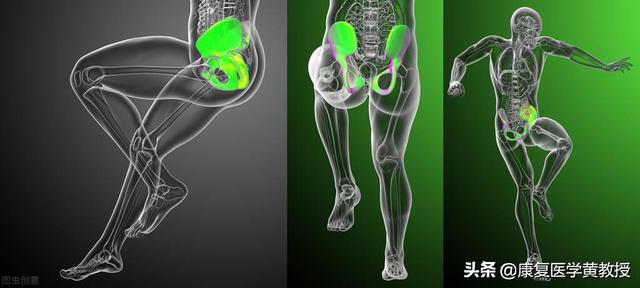

女性の身体解剖学的構造は男性とは本質的に異なる。

女性は生殖の役割を担っているので、女性の骨盤は比較的男性の骨盤よりも広く、それはまた、膝関節の力線につながる、また、特定の異常を持っている、我々は通常、女性の骨盤は、男性の骨盤よりも広いです。膝蓋骨の中点から脛骨結節までの線が、大腿四頭筋の引きつけの立位線と交差する角度をq角という。正常なq角は男性で10~15°、女性で12~18°である。 q角が大きいほど、膝蓋骨は横方向に動く傾向がある。女性の場合、座屈角度が大きいほど、スクワット時の膝蓋骨と大腿骨後面との摩擦が大きくなるため、多くの女性が膝蓋大腿部外側に痛みを感じやすくなります。

女性のq角の角度は男性より3°大きいだけと誰もが思うかもしれないが、デリケートな膝関節にとってこの3°の異常は、女性が膝痛を起こしやすいことを知るには十分である。人工膝関節置換術における1°のズレは、取り返しのつかない結果をもたらす可能性がある。

男女の構造は大きく異なる

私たちの祖先は集団で生活するようになり、労働を分担し始めた。男性は狩りをたくさんする必要があったため、背の高い体、強い脚、強い腕を発達させた。この時期の男女の違いは、生存の目的の違いによって大きくなった。